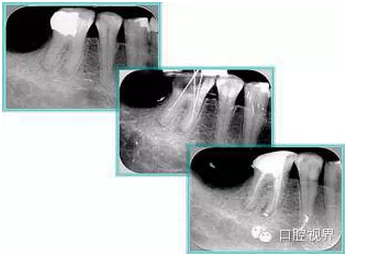

6. 術(shù)后 X 線片

術(shù)后 X 線片用來(lái)評(píng)定根管充填 長(zhǎng)度、致密度(管壁清晰、側(cè)枝)等指標(biāo)。

左圖為根管充填術(shù)后 X 線片。圖中可見(jiàn),根管充填較好。右下圖有白色小點(diǎn),為側(cè)方加壓導(dǎo)致糊劑擠出所致,表明根管充填比較致密。

致密、恰到好處的充填可去除干凈根管里感染灶,機(jī)體逐漸恢復(fù)。

多根牙時(shí)候需進(jìn)行偏移投照,正位投照無(wú)法說(shuō)明具體哪根牙根管充填效果。